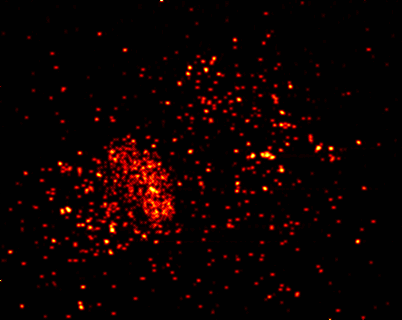

以下的紅點是被紅色螢光標註的免疫細胞,可以看到免疫細胞辨認出癌細胞後,透過抗原-抗體結合包圍癌細胞,再瓦解消滅癌細胞的過程。

在突變細胞還未發展成癌細胞前,它們被免疫細胞有效地控制及清除。就像原本是幾個壞人作亂,警察還能有效地捕捉和消滅壞人,但很多壞人聚集結盟形成了有組織規模的黑社會,原本的警察系統就難以對抗了,再加上黑社會可能會吸收警察入盟或派臥底進入警局,變成有內應的犯罪系統,就更難清除了。

以下是48小時的顯微鏡縮時攝影,可以細部看到T細胞辨認出癌細胞後,攻擊癌細胞並讓癌細胞瓦解癌細胞的過程。